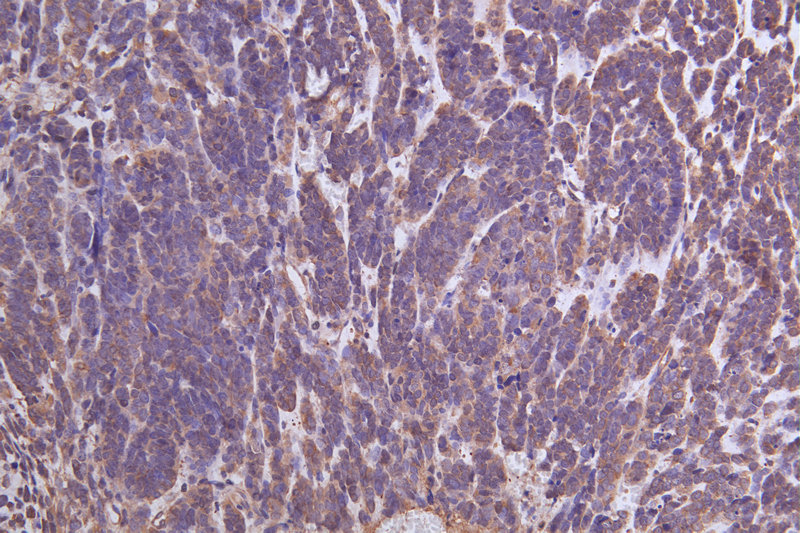

IHC image of CSB-RA824302A0HU diluted at 1:100 and staining in paraffin-embedded human endometrial cancer performed on a Leica BondTM system. After dewaxing and hydration, antigen retrieval was mediated by high pressure in a citrate buffer (pH 6.0). Section was blocked with 10% normal goat serum 30min at RT. Then primary antibody (1% BSA) was incubated at 4°C overnight. The primary is detected by a Goat anti-rabbit polymer IgG labeled by HRP and visualized using 0.05% DAB.

Immunohistochemistry of paraffin-embedded human endometrial cancer using CSB-PA026288LA01HU at dilution of 1:100